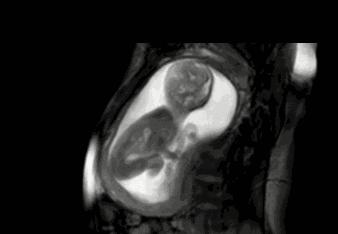

胎儿在孕妈肚子里的动作都是不一定的,有可能用脚踢一下,有可能用手锤一下,小雨就是将这每一个动作都计算为一次胎动。其实真正的一次胎动,是胎宝的一个连续的动作。一般这个计算时长在一分钟左右,或者在隔了有五分钟以上,再有胎动的时候记为第二次胎动。

有些孕妈比较心急,从20周,甚至16周就开始数胎动,其实这个月份数下来并不是很准。因为在这个阶段,孩子的胎动并不是很明显,频率也比较低。一般建议是在28周,也就是胎儿七个月的时候,孕妈开始数胎动。这个时间段的胎动最为活跃,孕妈也最需要注意胎儿的健康。